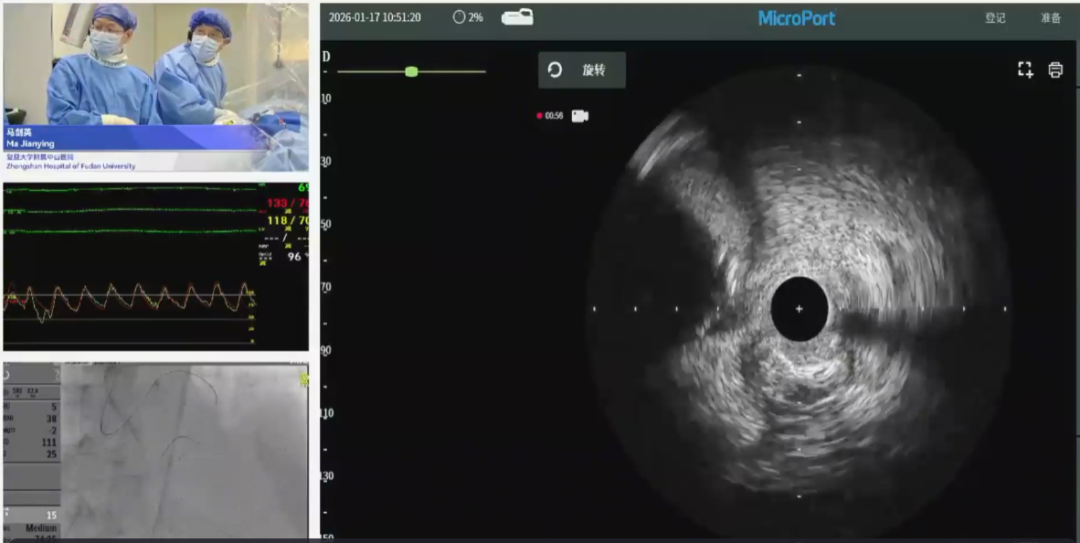

手术1:IVUS指导CTO精准介入

马剑英教授及厦门大学附属心血管病医院手术团队

首先,复旦大学附属中山医院马剑英教授协同厦门大学附属心血管病医院手术团队,展示了一例 IVUS如何指导CTO的开通、真假腔的判别及治疗方案的选择。患者为72岁男性,有长期高血压、吸烟史及十二指肠溃疡出血史,因反复胸痛入院。冠脉造影显示多支血管严重病变,合并LAD CTO。患者此前已完成LCX支架植入,本次手术重点处理LAD CTO。手术首先尝试正向开通LAD,先后通过对角支及间隔支侧支尝试开通,均未通过。随后转为经间隔支侧支成功开通后降支,并进一步通过后降支侧支逆向开通LAD。术中IVUS证实导丝走行路径为“真-假-真”腔,并提示LAD中段存在严重钙化。为充分预处理病变,团队采用旋磨对LAD中段钙化处进行处理,最终使用药物球囊完成LAD治疗。该病例充分体现了IVUS在高阻力复杂CTO病变中精准指导侧支开通、判断导丝位置、确认钙化范围等方面的重要价值,同时也展示了正向、逆向策略灵活转换与腔内影像及治疗技术整合应用在复杂冠脉病变处理中的策略意义。